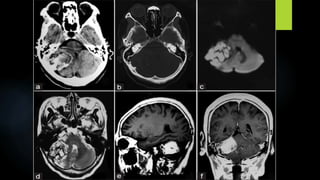

Ependymoma (contd.)

 MRI:

 The MR differentiation of ependymomas from other gliomas is related to their location &

morphology only.

 The post fossa ependymoma is lobulated soft tissue mass that appears to form a cast or mold

of the fourth ventricle & extrudes through its outlet foramina into the adjacent subarachnoid

cisterns

 The solid components are hypo – to isointense compared to brain on T1WI & hyperintense on

proton density & T2WI

 The cystic portions are slightly hyperintense to CSF on T1WI & hyperintense to brain on T2WI

 Intratumoral heterogeneity may represent necrosis , calcification , tumor vascularity or blood

degradation products

T2WI T1WI

T1 + C

FLAIR

DWI